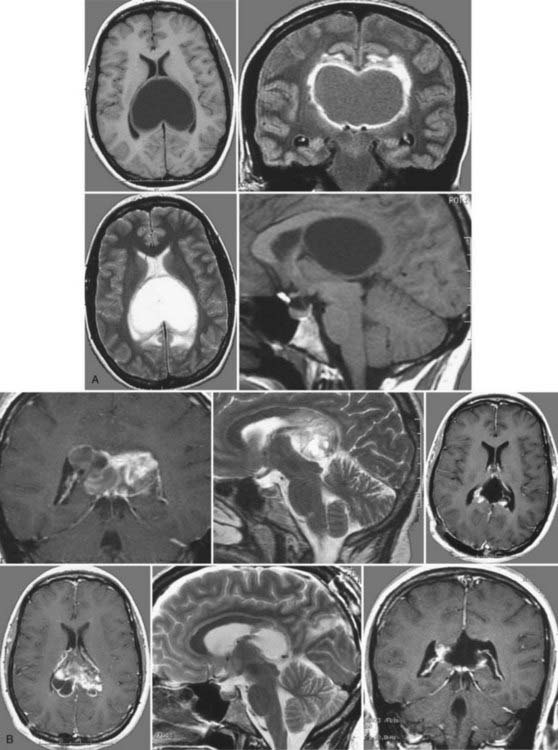

例如德国汉诺威国际神经外科研究所(INI)神经外科教授巴特朗菲(Helmut Bertalanffy),他在一份研究报告中表示,其曾治疗的患者中有一名33岁的孕妇,就诊前具有严重的头痛、平衡感失调和记忆力缺失的症状。在为这名孕妇进行磁共振图像(MRI)检查时发现占据两侧脑室后部的毛细胞型星形细胞瘤。

教授在这名孕妇平稳分娩后,为其经胼胝体前入路进行手术,并完全切除了肿瘤。术后,这名患者除出现短暂的轻度记忆缺失之外,后续并没有出现任何神经或认知上的缺陷,并且教授通过随访MRI对照,排除了肿瘤的复发。